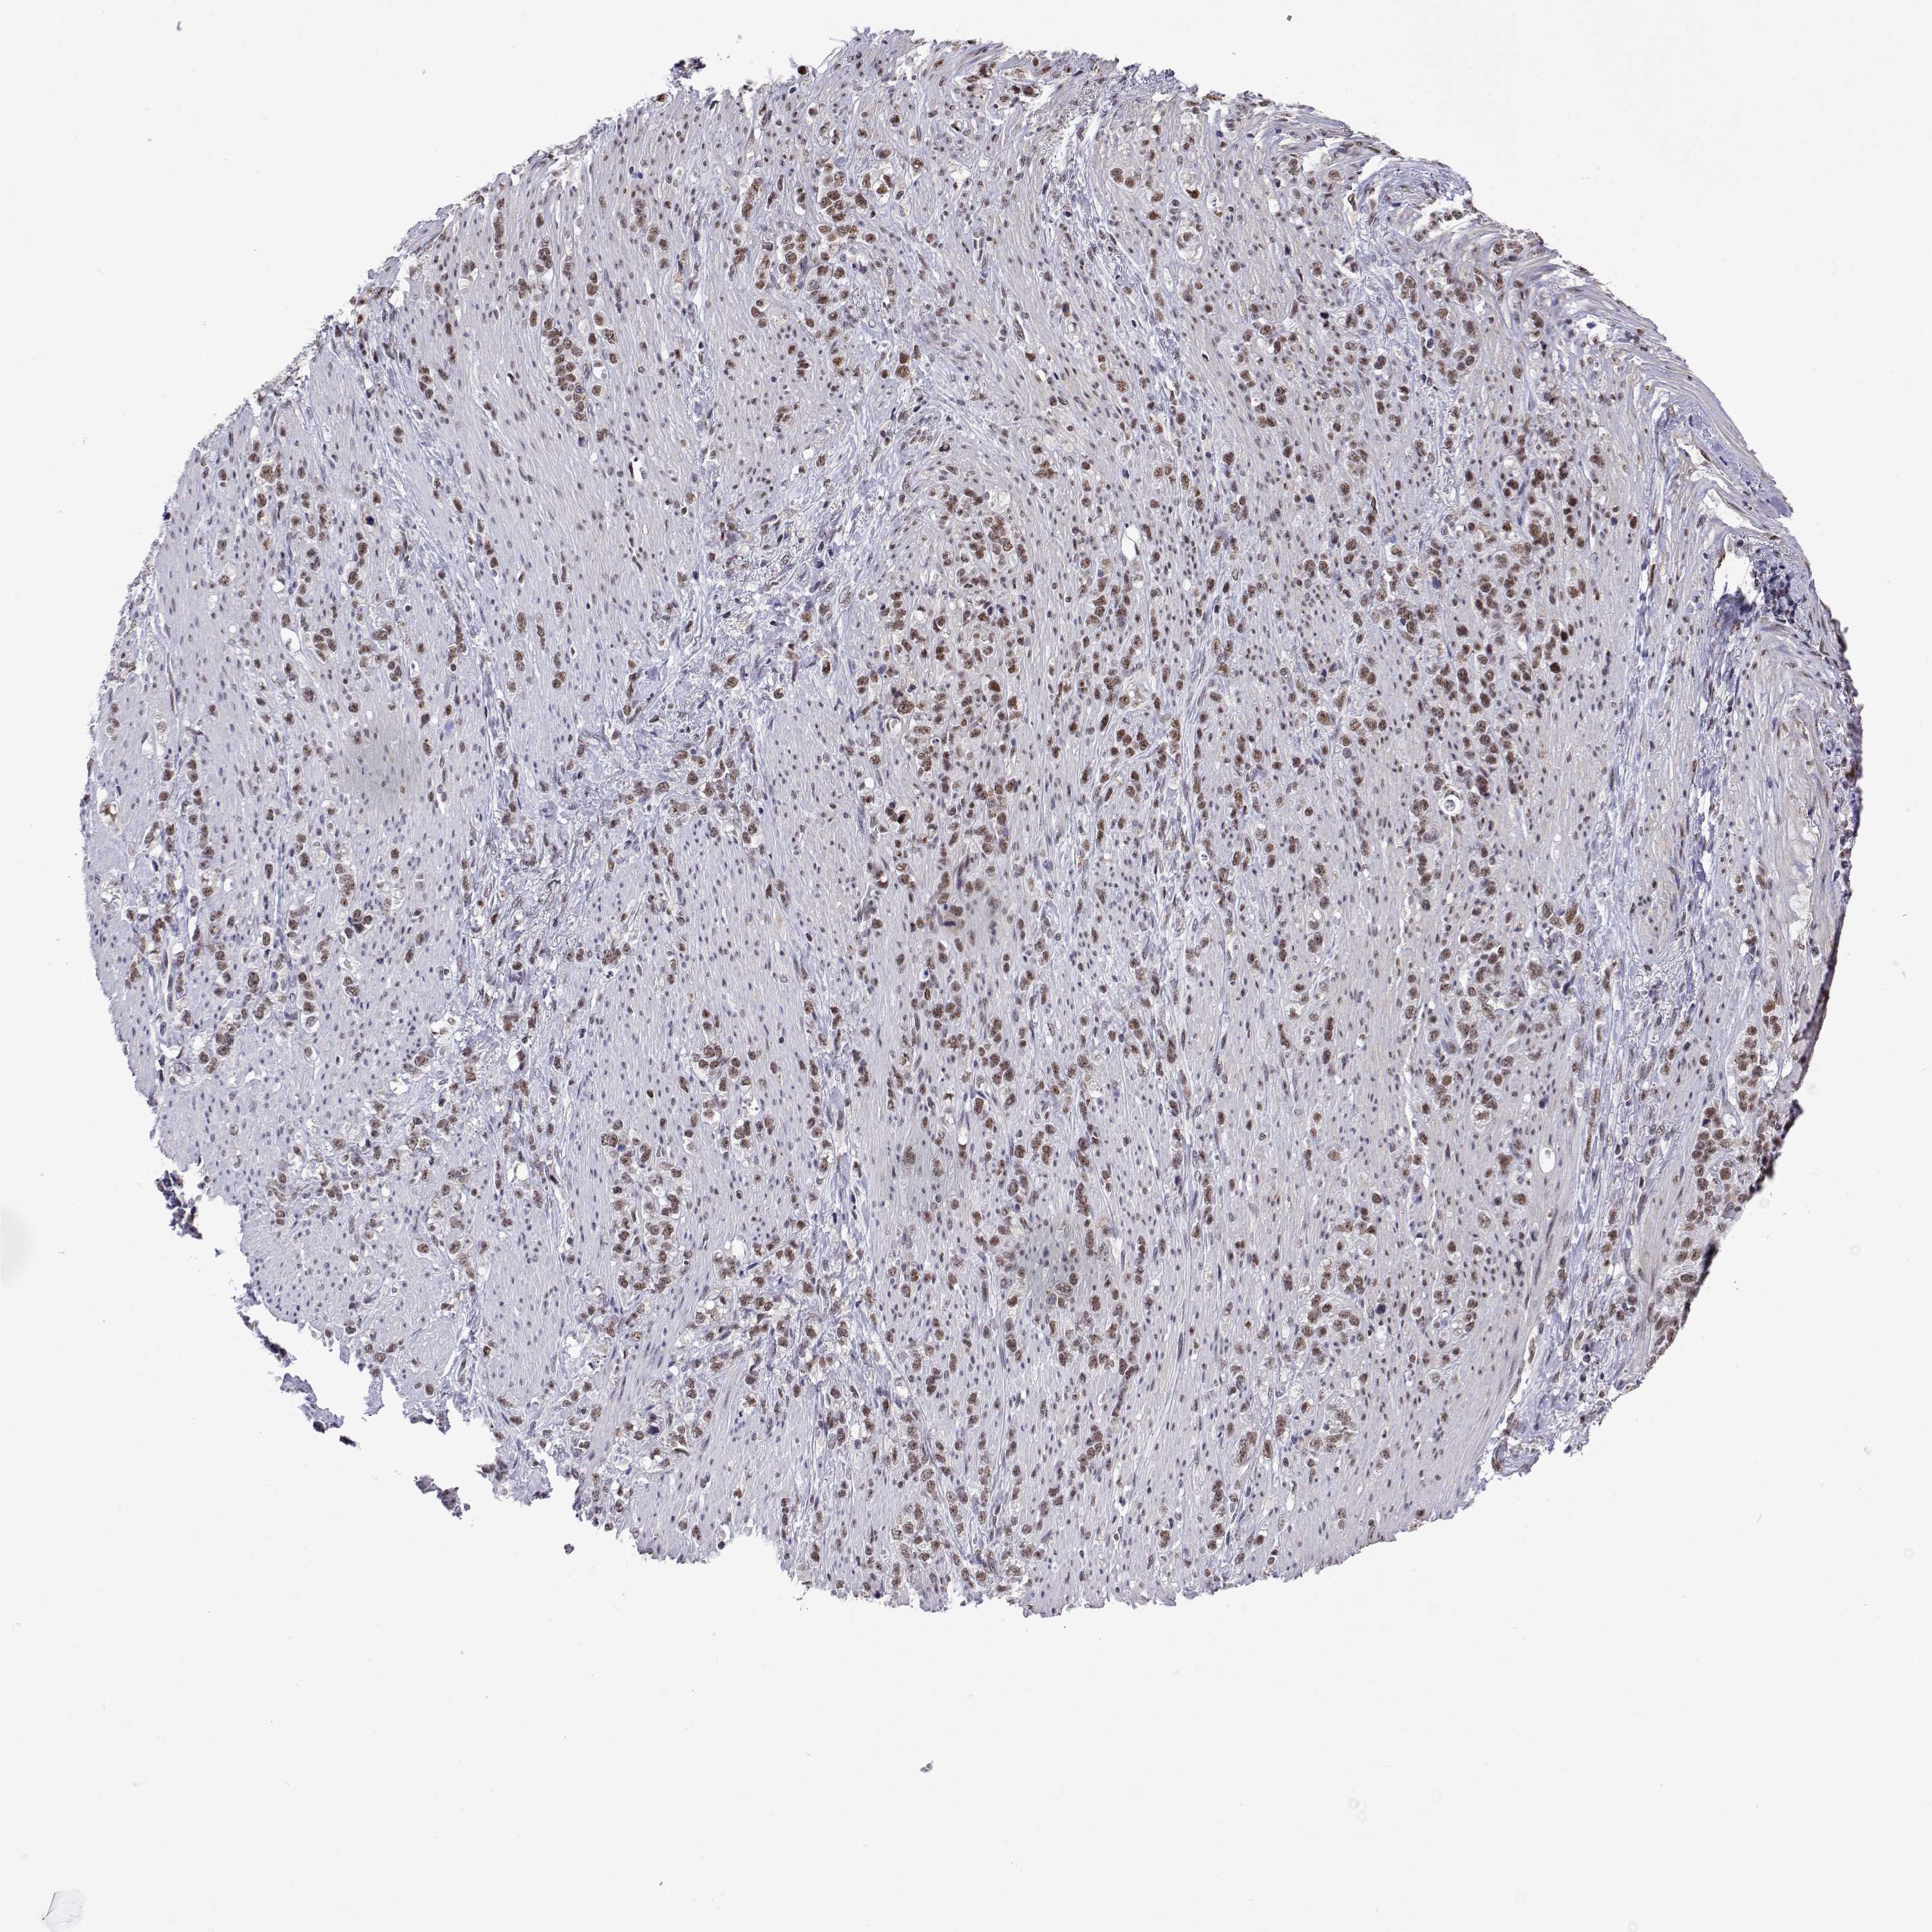

STOMACH CANCER - Protein expressioni

A mouse-over function shows sample information and annotation data. Click on an image to view it in a full screen mode. Samples can be filtered based on level of antibody staining by selecting one or several of the following categories: high, medium, low and not detected. The assay and annotation is described here.

Note that samples used for immunohistochemistry by the Human Protein Atlas do not correspond to samples in the TCGA dataset.

Antibody stainingi

Antibody staining in the annotated cell types in the current human tissue is reported as not detected, low, medium, or high, based on conventional immunohistochemistry profiling in selected tissues. This score is based on the combination of the staining intensity and fraction of stained cells.

Each image is clickable and will lead to virtual microscopy that enables deeper exploration of all samples and also displays staining intensity scores, fraction scores and subcellular localization as well as patient and tissue information for each sample.

Antibody HPA018419

Antibody HPA048790

Staining

High

Medium

Low

Not detected

Intensity

Strong

Moderate

Weak

Negative

Quantity

>75%

75%-25%

<25%

None

Location

Nuclear

Cytoplasmic/membranous

Cytoplasmic/membranous,nuclear

Adenocarcinoma, NOS